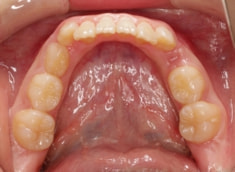

治療後(1年5ヶ月後)